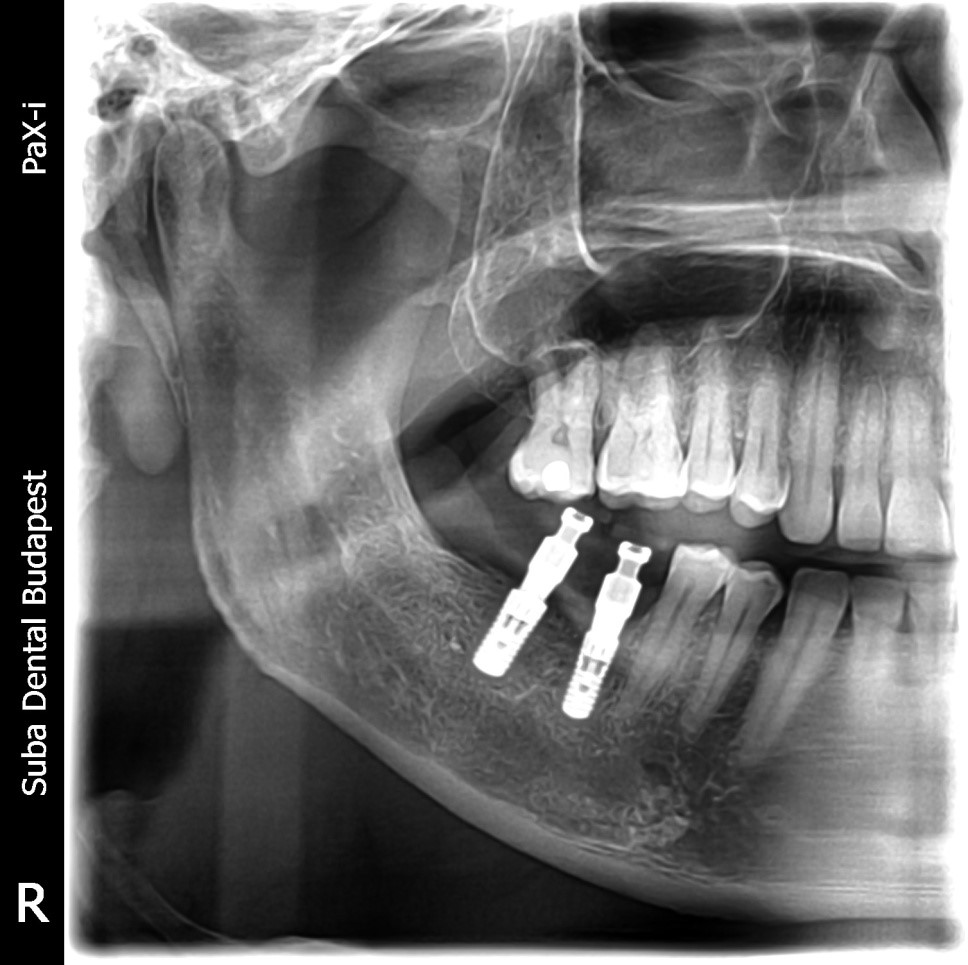

Panoramic radiograph following the installation of the Straumann implants in place of lower right teeth no. 46 and 47.

First treatmentAt the first treatment a CBCT (Cone beam computed tomography) scan was made in order to examine residual bone mass in 3 dimensions prior to implantation. Based on the CT scan it was found that the bone mass in the area of the missing lower molars was sufficient for an implant. 2 Straumann implants of diameters 4.1 mm and 4.8 mm were installed, reckoned as ideal for the replacement of molars. The primary stability of the implants was over 30 Ncm at implantation, gingiva formers were therefore used to seal the implants straight away.